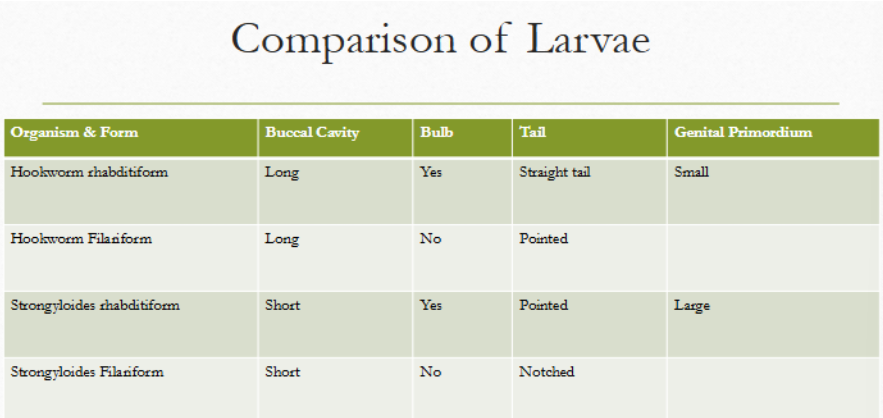

rhabditiform vs filariform

strongyloides stercoralis rhabditiform larvae

Short and sexy

first-stage larva as passed in the feces

esophagus is short (much less than 40% of the body) and distinctly bulbed, the short mouth capsule, and the large genital rudiment (GR)

the latter 2 characteristics distinguish these larvae from those of the hookworms

simple pointed tail

strongyloides stercoralis filariform larvae

esophagus extends to 40% of the body length

Focus carefully to notice the notched tail

Length of esophagus and the notch in the tail allow you to distinguish between the two larval forms

The esophagus does not have a bulb

hookworm rhabditiform larvae

Long buccal cavity

More than the width of the body

Genital primordium NOT visible

Esophagus is bulbed

strongyloides rhab vs filariform

rhabditiform: short buccal cavity; esophageal bulb; pointed tail; large genital primoridum

filariform: short buccal cavity; no esophageal bulb; notched tail

hookworm rhab vs filariform

rhabditiform: long buccal cavity; esophageal bulb; straight tail; small genital primordium

filariform: long buccal cavity; no esophageal bulb; pointed tail

strongyloides rhab vs hookworm rhab

strongyloides: short buccal cavity; esophageal bulb; pointed tail

hookworm: long buccal cavity; esophageal bulb; straight tail

strongyloides filariform vs hookworm filariform

strongyloides: short buccal cavity; no esophageal bulb; notched tail

hookworm: long buccal cavity; no esophageal bulb; pointed tail